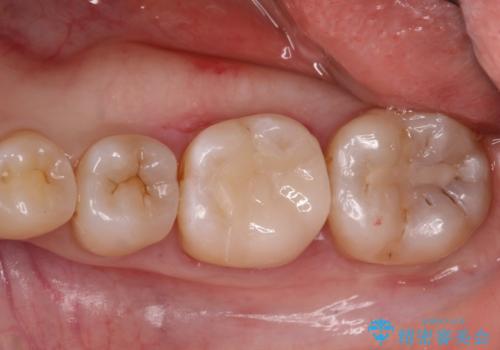

[ メタルフリー治療 ] 金属のない口腔内にしたい

![[ メタルフリー治療 ] 金属のない口腔内にしたいの症例 治療後](https://seimitsushinbi.jp/wp/wp-content/uploads/2021/09/7dd01ef5eeb5bcef896adc1f4413dba9-500x350.jpg?v=1632299935)